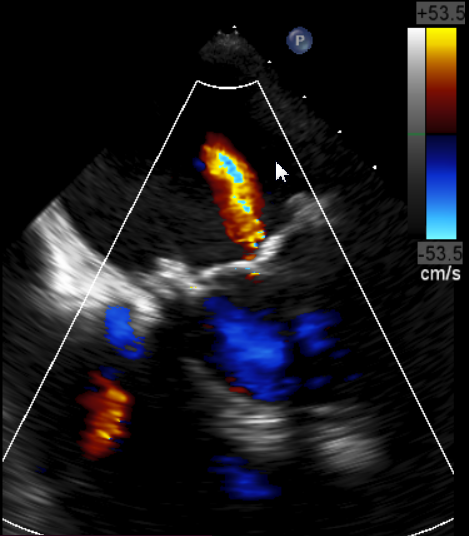

原生物瓣少量反流

过瓣流增快,呈“五彩状”

CDFI提示过瓣血流通畅

CDFI示少量瓣周漏